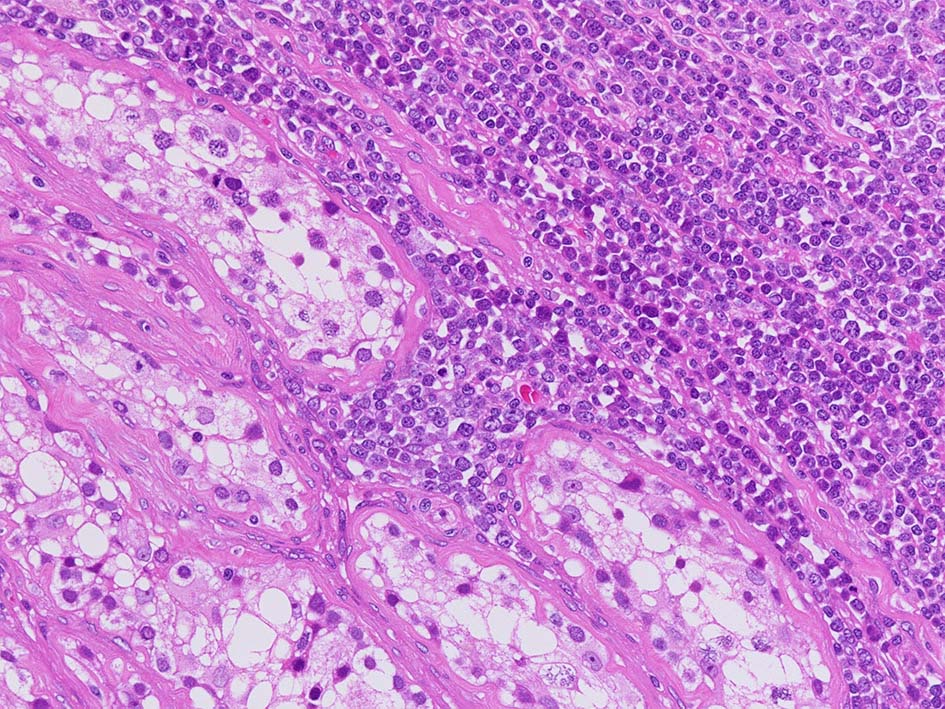

増殖巣では精細管は消失, 萎縮. 腫瘍境界部での浸潤所見がある.

Extranodal NK/T-cell lymphoma, nasal type of the testis